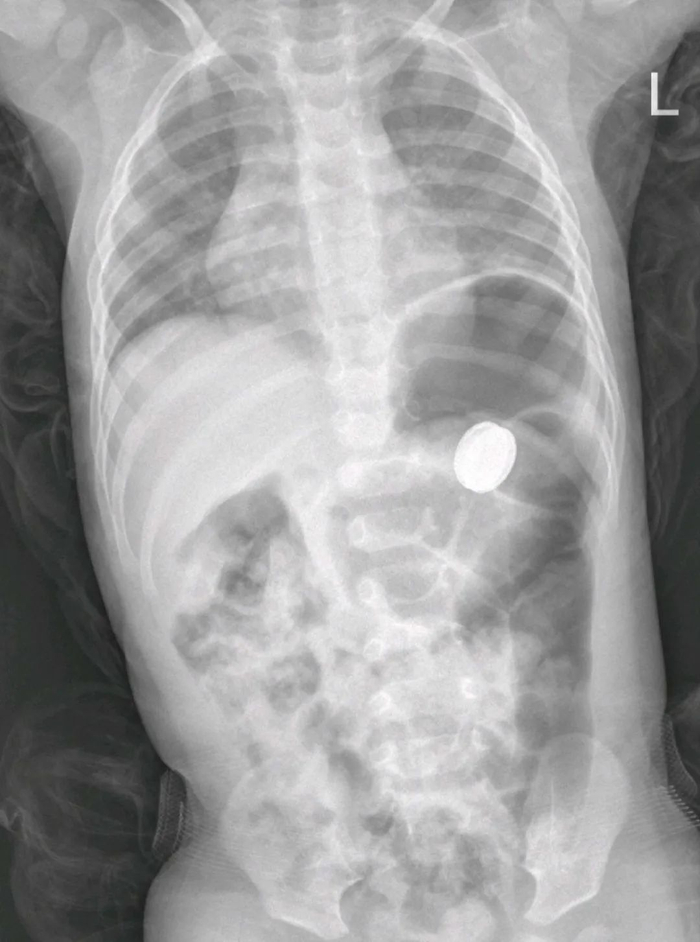

医院再次复查正位腹平片,发现电池掉进了胃内,遂转诊到小儿外科。考虑到胃酸腐蚀电池后会引起电池内部化学物质泄露,引起中毒及消化道损伤,小儿外科立即收住院,同时联系消化内科及麻醉科,准备做手术,通过胃镜探查并取出电池。

术后再次复查,看到电池依然在胃腔里,小儿外科主任医师苏泽礼综合考量后,提出诊疗方案:有手术指征,且不能等太久。虽然第一次胃镜取异物失败,但直接开腹手术探查,对孩子的损伤比较大。因此等胃里面的食物残渣排空后,再做一次胃镜探查,并尝试异物取出,必要时再开刀行手术探查!

3月5日早晨,苏泽礼统筹指挥,多个科室密切配合,再次为孩子做胃镜探查,这一次,胃里的食物残渣已经排空了,可以清楚地看到电池,医生操作胃镜,利用网篮抓取电池后,慢慢往上提。但是到达咽喉部位时,卡住了,这里是食道生理狭窄处,而胃镜抓钳比较软,抓力不够,尝试了好几次都无法把电池取出来。